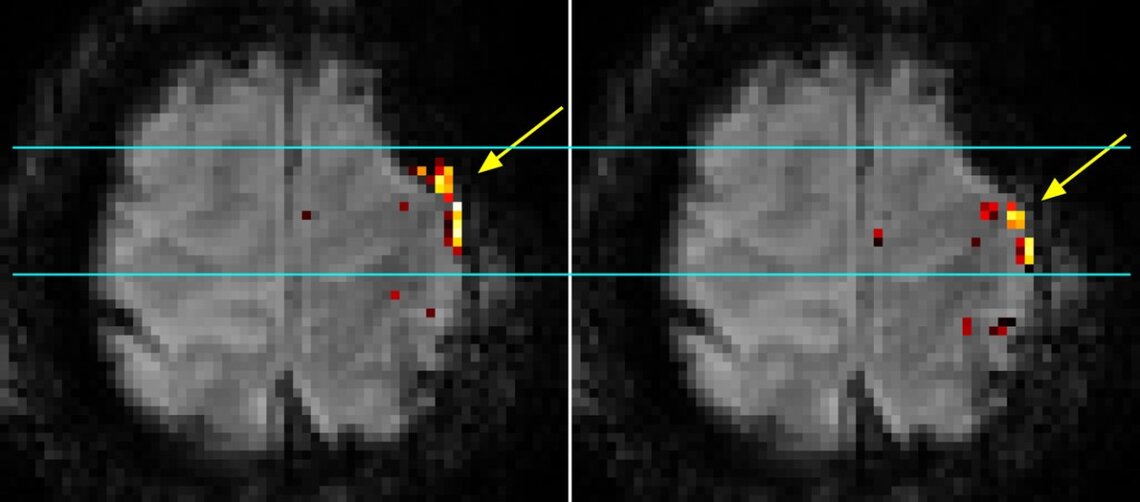

Mit der höheren Magnet-Feldstärke kann die Gehirnfunktion schneller und mit höherer Auflösung abgebildet werden: „So können wir etwa erkennen, ob sich das Sprachzentrum durch einen Tumor verschoben hat. Leider nehmen Verzerrungen des Magnetfelds durch Knochen, Gewebe oder Luft ebenfalls zu. Das wirkt sich auf die funktionellen Bilder aus“, betont der Projektleiter von der Universitätsklinik für Radiologie und Nuklearmedizin. Ohne Bildkorrektur würden funktionelle Areale nicht genau genug in der Anatomie verortet.

In fünfjähriger Forschung wurde ein dynamisches Bildkorrekturverfahren entwickelt, das sich als internationaler Standard für alle fMRT-Studien eignet: für die präoperative Planung, aber auch für Grundlagenforschung in der Neurowissenschaft. Vor Beginn der funktionellen Messungen wird der Anteil der Maschine an den Signalen genau bestimmt. Diese Korrekturfaktoren werden nach den Messungen in der Bildberechnung abgezogen. Mithilfe von 7T entsteht so eine präzise 3D-Landkarte des individuellen Gehirns, in der funktionelle Hirnareale genau mit der Gehirnanatomie zusammenpassen. Neurologinnen und Neurologen können dann entscheiden, ob eine Operation sinnvoll und möglich ist, und welche Teile des Gehirns um jeden Preis geschont werden müssen. In einem Folgeprojekt will das Team die Methode weiterentwickeln, um den bestmöglichen Einsatzort für Sonden zur Tiefhirnstimulation bei Parkinson-Patientinnen und -patienten zu bestimmen.